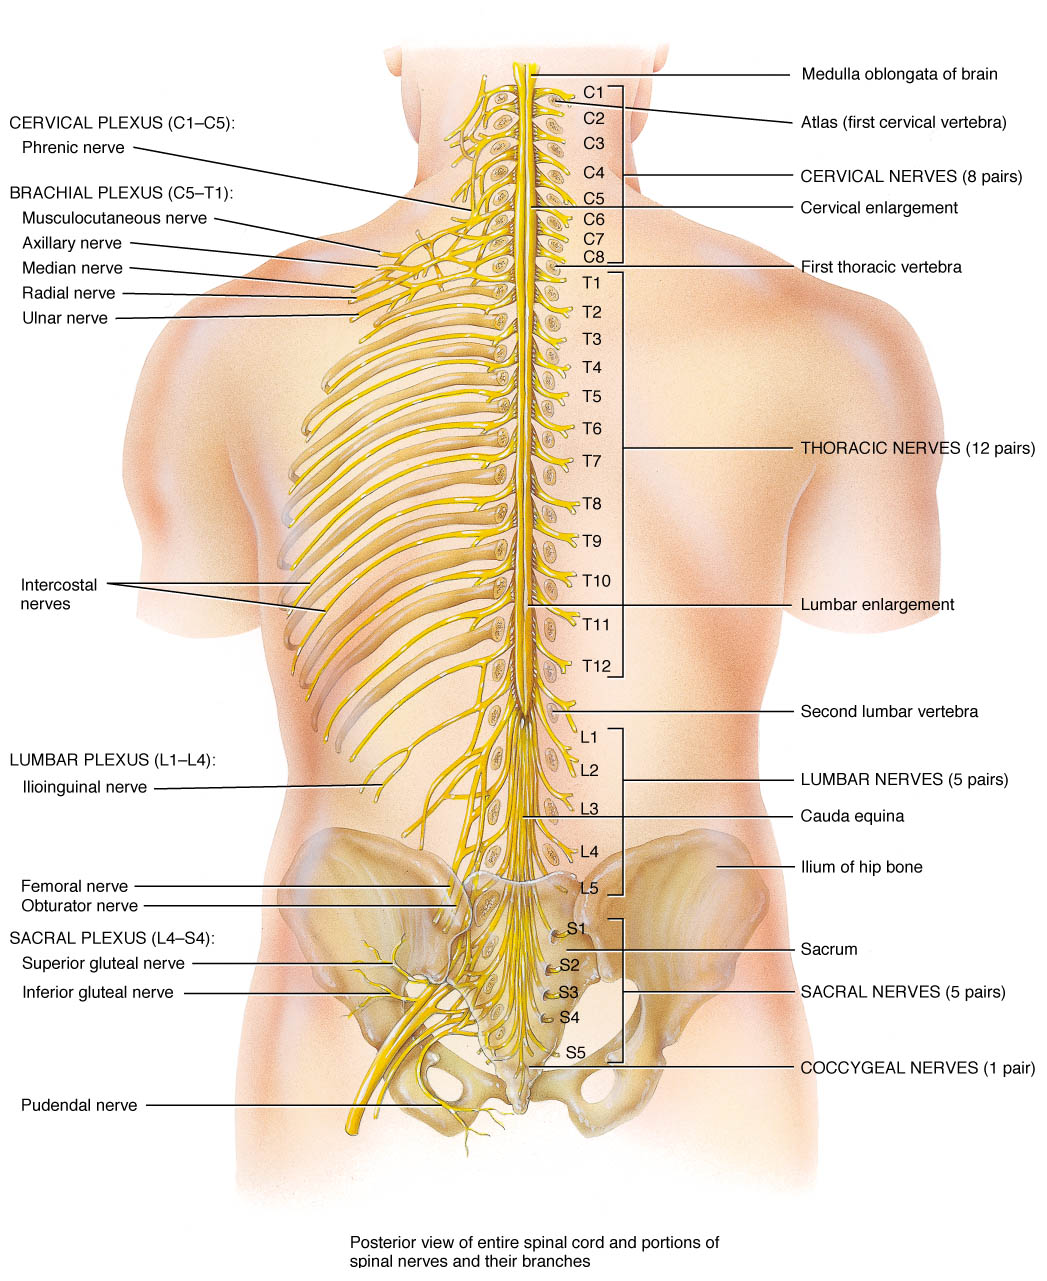

Spinal Cord Injury Levels | Bone and Spine | Spinal cord injury, Spinal …

Pin by Michelle Evans on med school | Spinal cord, Spinal nerves …

Pin by Allison Atwill on OT Grad in 2021 | Spinal cord, Spinal cord …

anatomy+of+the+sciatic+nerve | Nerves Of Spine | Healing remedies …